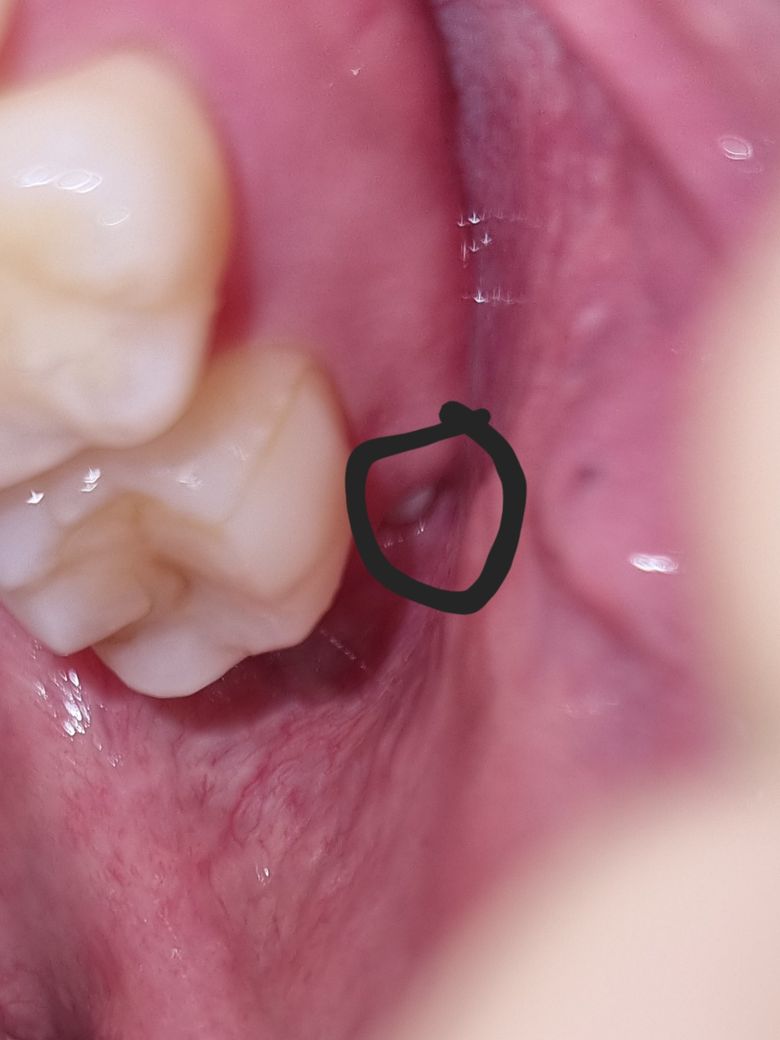

안녕하십니까 선생님들 다름이 아니라 제 치아를 살펴보다가 이런걸 발견했는데 혹시 이게 뭔가요?? 사랑니인지 아니면 염증인지 뭔지

궁금합니다

염증으로보이지는 않고 사랑니로 보입니다. 사랑니는 웬만하면 발치를 하시는 것이 좋습니다.

사진으로만 봤을 경우에는 사랑이로 보입니다.

사랑니가 부분적으로 맹출 되었을 경우에는 사진과 같이 흰색으로 보일 수 있습니다.

사진상으로 보이는 건 잇몸에 생긴 구내염증일 것 같고 원인은 잇몸 내부의 사랑니일 수도 있고 아니면 피곤해서 생긴 염증일 수도 있습니다

별도로 통증이 있다면 치아 신경이나 잇몸과 관련하여 농이 잡힌 것일 수도 있습니다

현재 사진상으로는 구내염으로 보이며, 보다 정확한 확인을 위해서는 치과 진료를 받길 권합니다.